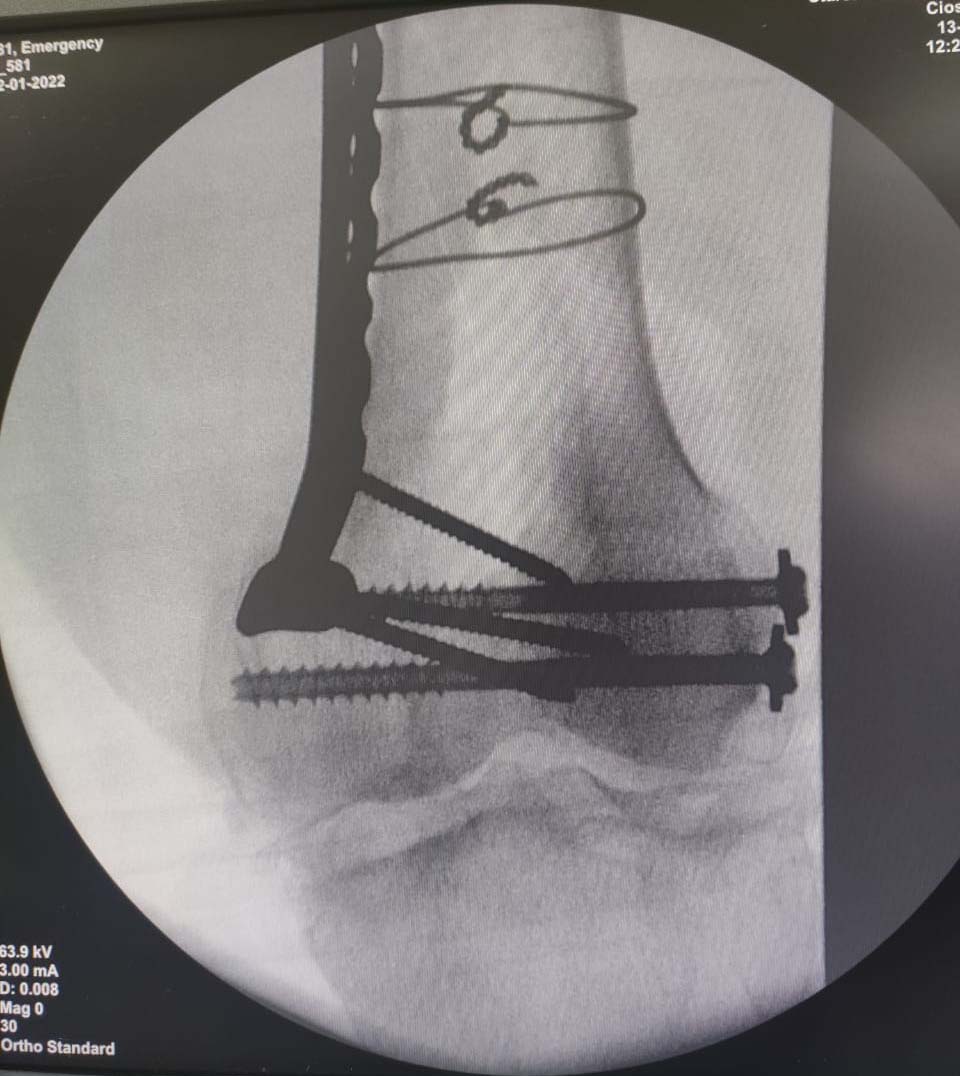

Trauma Fracture